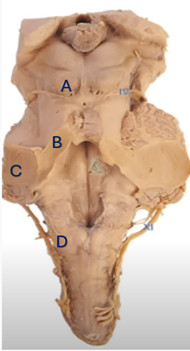

Q3. In the given image, which region is correctly paired with its corresponding brain structure?

- Middle cerebellar peduncle

- Fasciculus cuneatus

- Superior cerebellar peduncle

- Inferior colliculus

- 1-A, 2-B, 3-C, 4-D

- 1-B, 2-C, 3-A, 4-D

- 1-D, 2-C, 3-A, 4-B

- 1-C, 2-D, 3-C, 4-A

Answer – C